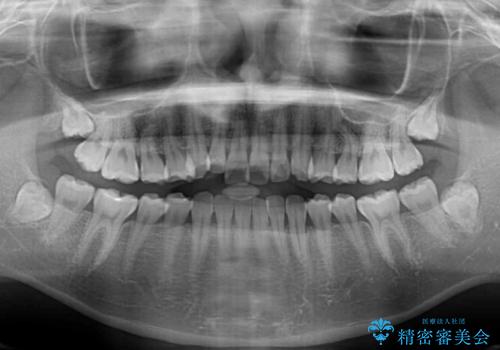

口元の突出感は強くなかったため非抜歯矯正での対応となりますが、捻転を改善する際に上顎前歯が前突する可能性があったため、上顎臼歯部にアンカースクリューを使用して、歯列が前方に転位しないようにすることとしました。

ワイヤー矯正でもインビザラインでも対応可能でしたが、上顎歯列が前方位であるときには、ワイヤー矯正の方がより良い仕上がりとなる可能性が高いため、ワイヤー矯正をおすすめいたしました。